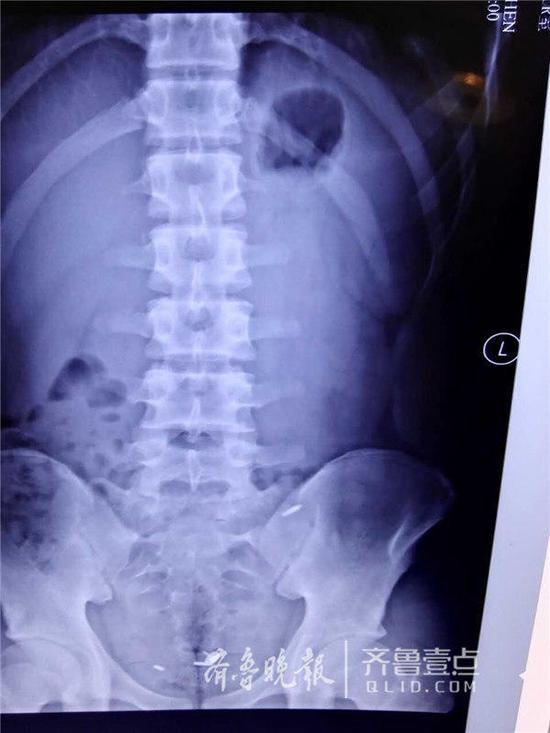

因与同学打赌,济南一名16岁的少年竟口吞一枚图钉,并将三个圆珠笔芯头从肚脐生生塞入腹腔中。事发后,少年被送至山东大学齐鲁医院急救。医生们经过4个小时的艰难寻找,才通过腹腔镜将三个圆珠笔芯头取出,而那枚图钉也在第二天被幸运地排出体外,整个过程十分惊险。

7日,一名16岁的少年王川(化名)被送到山大齐鲁医院进行抢救,医护人员介绍说,来的时候少年表情轻松,但他的讲述却让所有人都吓了一跳。原来,王川因为跟同学打了一个200块钱的赌,吞下了一枚图钉,后来又把三个圆珠笔芯的头通过肚脐塞到了肚子里。而无论是图钉还是笔芯头,都很尖锐,一旦划破肠道或是腹腔后果不堪设想。

急诊外科副主任李鹏宇介绍说,图钉当时已经在消化道中“前进”,由于肠镜取钉可能造成穿孔,加之之前一些案例中图钉被排出体外的可能较大,医生们的首选方案是给王川服下石蜡,希望图钉能随大便排出,同时准备而一旦发生穿孔,会立刻进行手术;另一方面,他们打算通过手术把王川肚子里的圆珠笔芯取出来。

幸运的是,在8日一早,王川排便时,这枚图钉果真被拉了出来。另一面,医生们开始了跟笔芯头斗智斗勇的艰难过程。

“非常难找。”李鹏宇说,王川年龄还小,为了减少创伤,他们在王川的肚脐和左右腹部各打了一个小孔,然后通过腹腔镜进行探查,但没想到在艰难地找到一个圆珠笔芯头后就再也找不到了。“由于翻找,笔芯头一直在换地方,一会在上面,一会在下面;肠子的大网膜、肠间隙非常多,情况复杂。”术中,一度医生们考虑或许只能通过创伤大的开腹手术将其取出,但考虑到孩子年龄,又坚持了下去。终于,历经了4个小时的艰难寻找,才终于把三个长1厘米左右的笔芯头给取了出来。